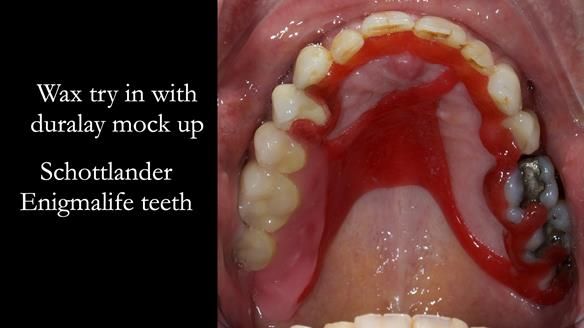

Welcome to Newsletter 64. I'll walk you through the process of providing a Mk 2 metal-based partial denture (RPD), for Ian a retired Veterinary Surgeon aged 78. The RPD was made at an increased vertical dimension and acted as an occlusal stabilisation splint - reducing the wear and bite force on the remaining natural teeth.